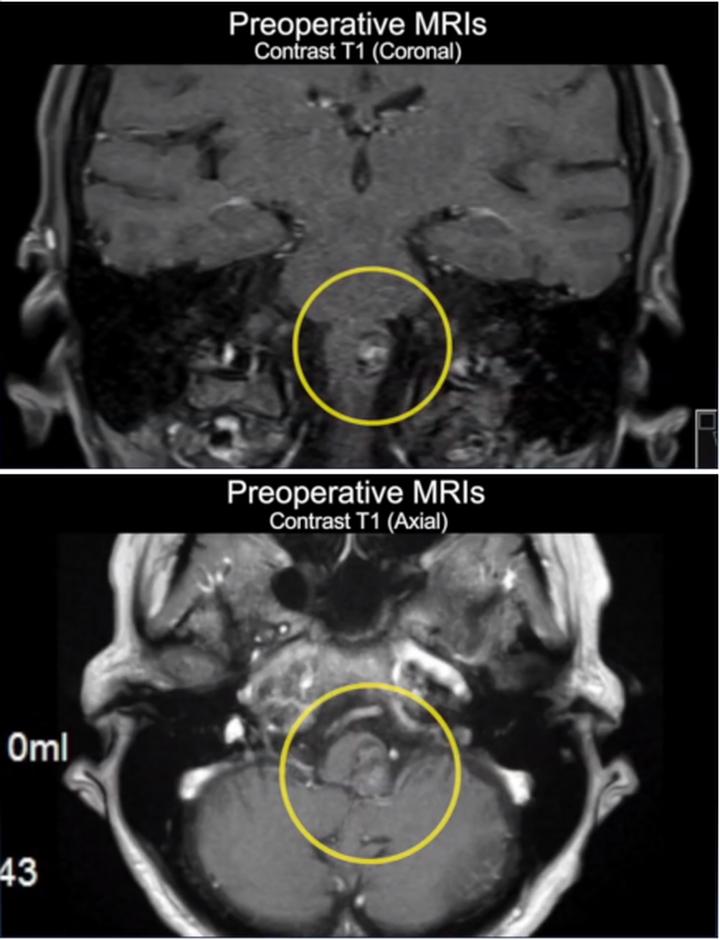

术前影像学检查

图2:术前MRI显示左侧延髓外侧有一个16毫米圆形病变,提示出血性海绵状瘤,病灶的大小比第一次出血后大。